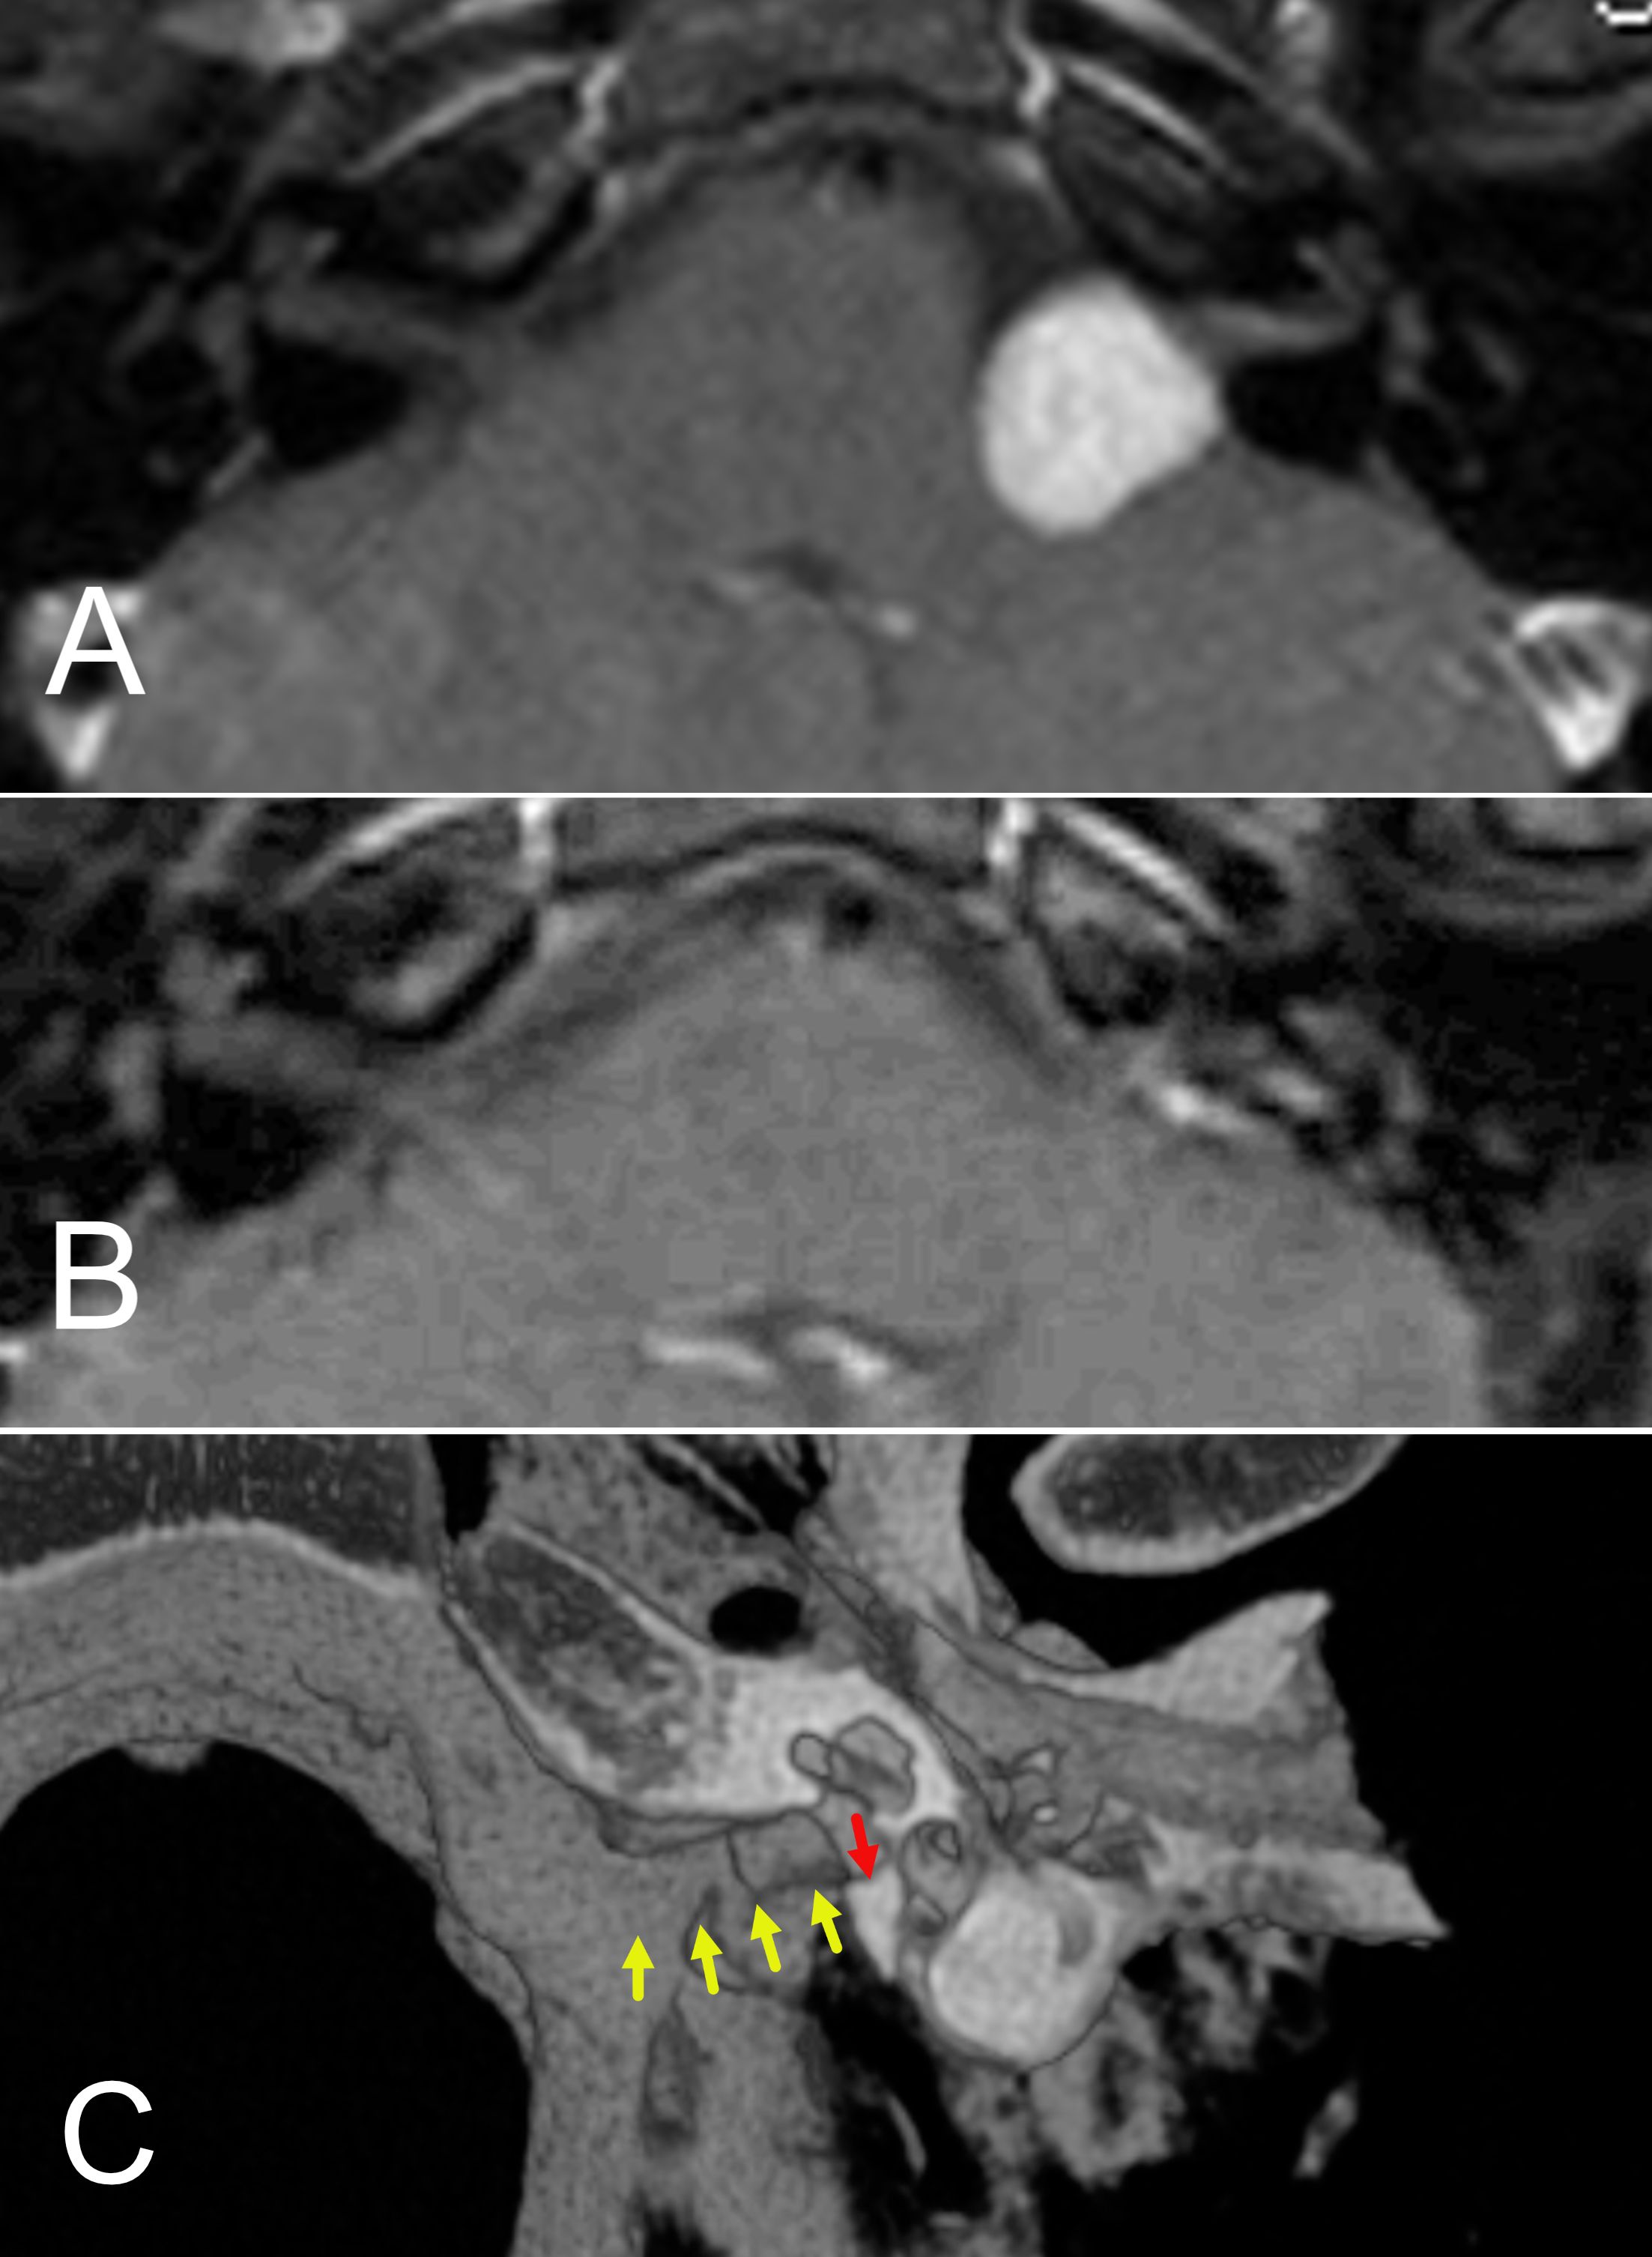

Introduction: Acoustic neuroma (AN) is a benign tumor of the vestibulocochlear nerve, with increasing detection due to improved imaging. Treatment decisions are complex, requiring an individualized approach based on tumor size, location, growth rate, and patient-specific factors such as hearing and vestibular function. Results: Treatment options include observation, microsurgery, and stereotactic radiosurgery. Hearing preservation is prioritized in select cases using middle cranial fossa or retrosigmoid approaches, while translabyrinthine surgery is preferred for larger tumors or disabling dizziness. Stereotactic radiosurgery offers a non-invasive alternative but has variable long-term hearing outcomes and potential tumor regrowth. Vestibular rehabilitation is essential post-treatment, particularly after surgical resection. Discussion: Decision-making depends on patient age, tumor progression, and symptom severity. Younger patients with small tumors may benefit from early intervention to preserve hearing, while older patients with severe imbalance achieve better quality-of-life outcomes with surgery. Stereotactic radiosurgery remains an option for patients unable to undergo surgery, though its long-term efficacy and side effects require careful consideration. A multidisciplinary approach is essential to optimize treatment outcomes. Summary: AN management must be tailored to individual patient profiles. This review integrates current literature and expert clinical experience to guide otolaryngologists, neurologists, and oncologists in treatment planning. Future research should refine treatment algorithms and improve functional outcomes.